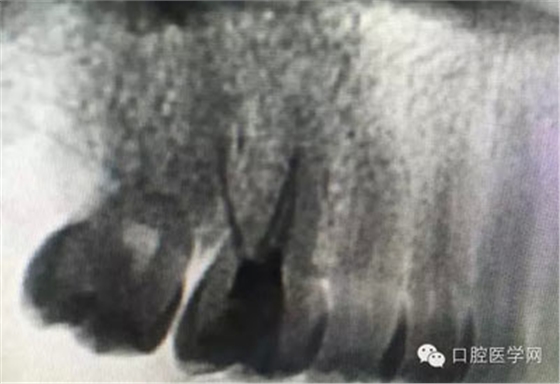

這是一例外院樹脂修復(fù)后十個(gè)月出現(xiàn)牙髓炎癥狀的患者。遇到這樣子的患者大家會(huì)怎么做,證明選擇,還有就是可做可不做治療的如何去平衡。